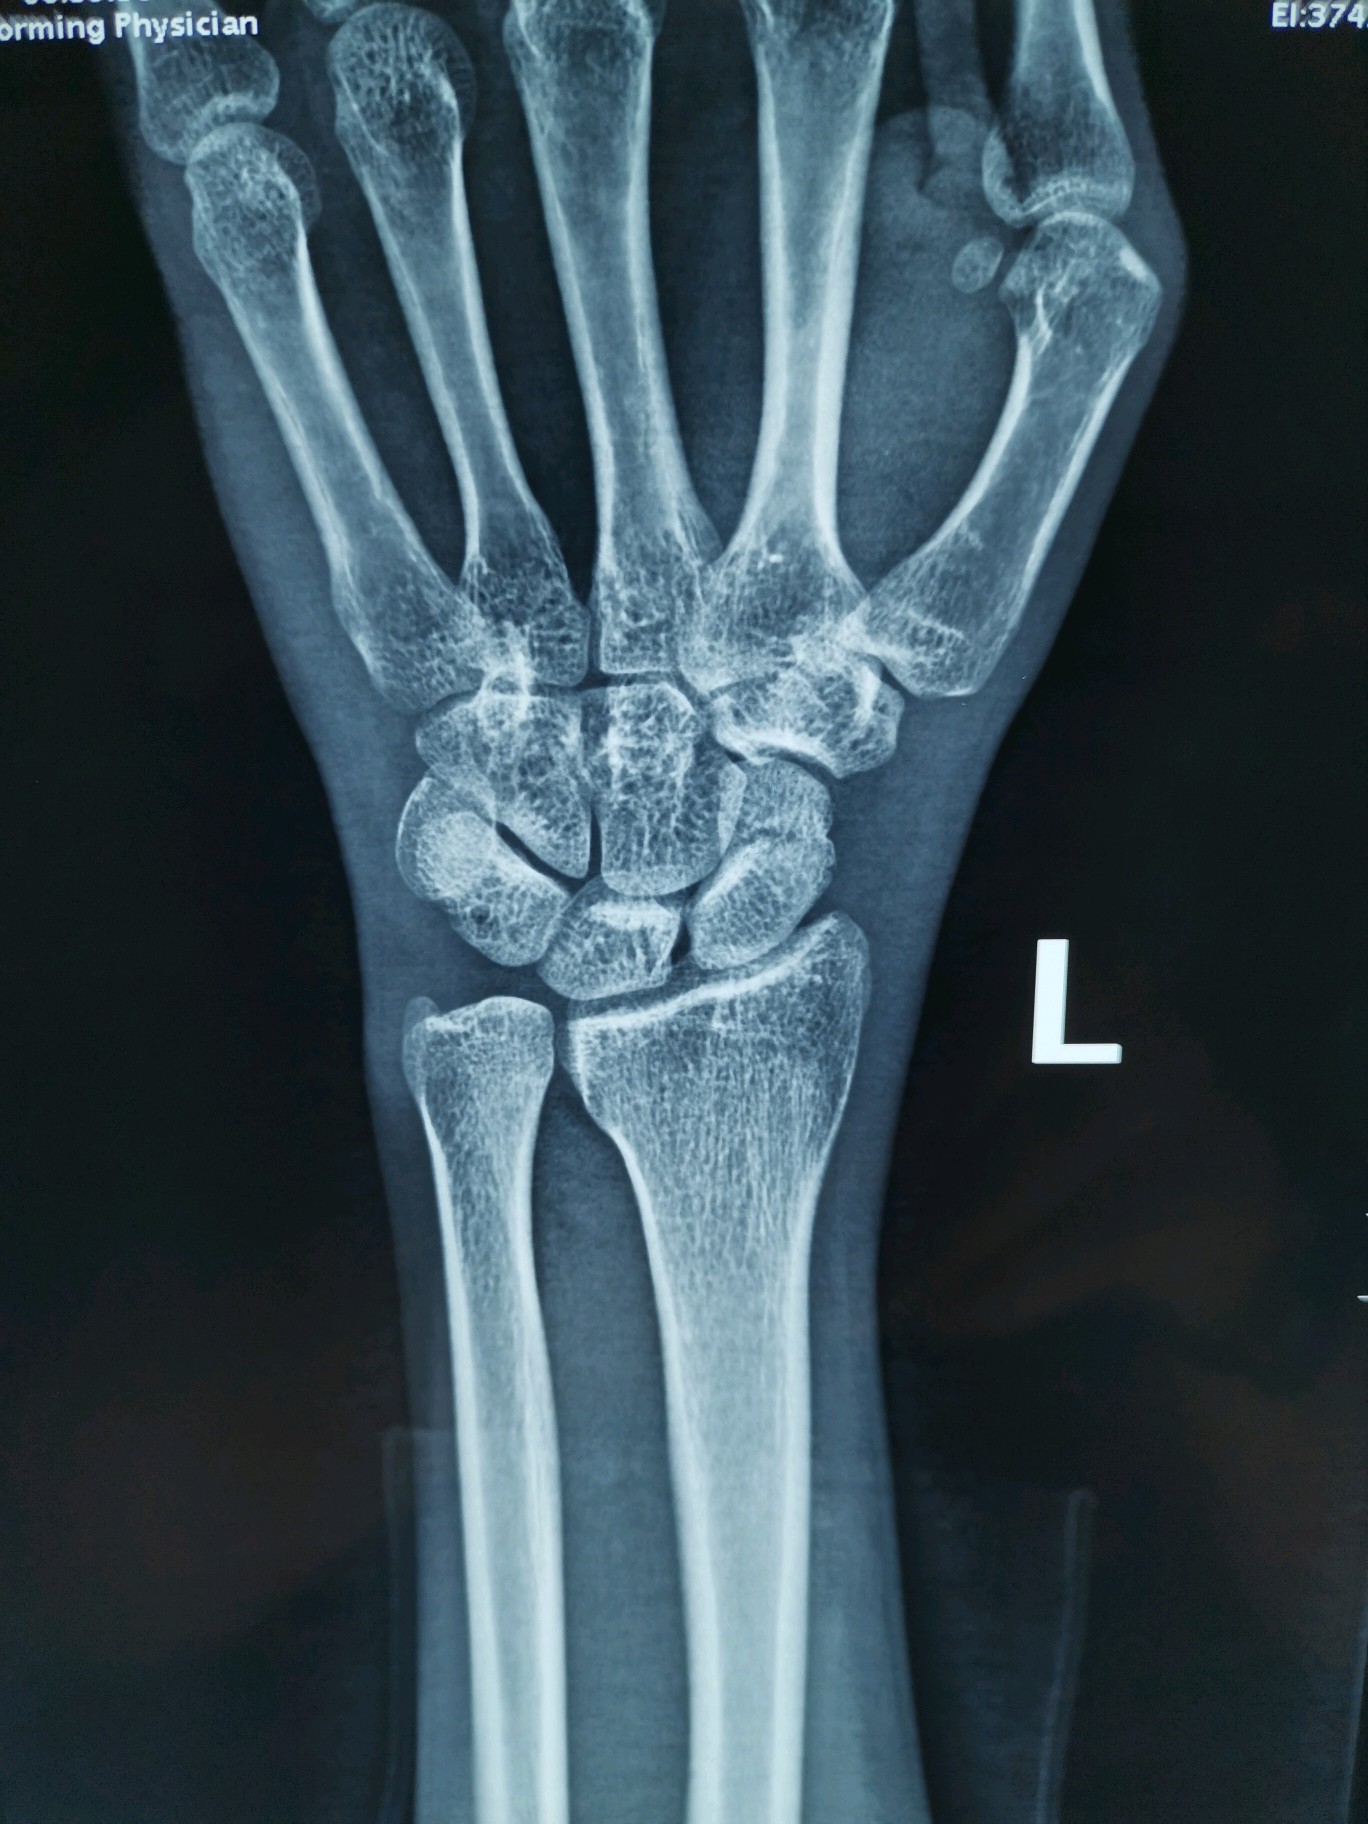

图片发自160医生app13左腕舟骨骨折13图片发自160医生app13皮肤

左手手腕舟骨骨折,这受伤程度严重吗?目前已夹板固定敷药8天.

左手舟状骨骨折